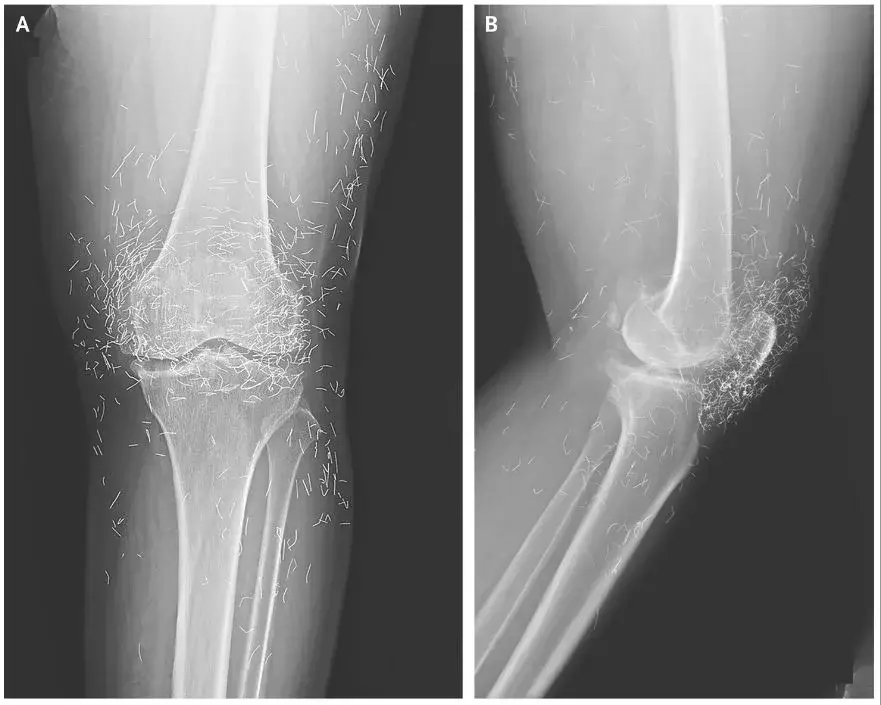

Pihak medis menjelaskan pasien awalnya datang ke rumah sakit dengan keluhan lutut yang terasa sangat nyeri. Setelah dilakukan pemeriksaan lebih lanjut, hasil rontgen menunjukkan adanya perubahan bentuk pada tulang kering bagian dalam lutut yang tampak menebal dan mengeras.

Selain itu, pertumbuhan tulang kecil atau bone spurs juga muncul di sekitar sendi lutut. Pada saat yang sama, dokter melihat adanya bintik-bintik putih dalam jumlah besar yang ternyata merupakan benang emas.

Temuan itu kemudian diidentifikasi sebagai bagian dari prosedur akupunktur dengan teknik khusus. Benang emas steril tersebut sengaja ditanamkan di jaringan tubuh pasien untuk memberikan stimulasi jangka panjang.

"Ia kemudian datang ke rumah sakit karena lututnya sangat nyeri. Rontgen pada lutut kirinya menunjukkan tulang kering bagian dalam menebal dan mengeras. Ada juga pertumbuhan tulang kecil di sekitar tulang kering dan tulang paha dekat sendi lutut," imbuhnya.

Temuan mencengangkan muncul dalam hasil rontgen berikutnya. Ratusan benang emas terlihat jelas menempel di sekitar sendi lutut.

"Dokter juga melihat ratusan bintik putih pada hasil rontgen di sekitar sendi lutut, yang ternyata adalah benang emas kecil," ungkapnya.

Dari pemeriksaan lanjutan, dokter mengetahui bahwa benang tersebut memang sengaja ditanamkan. Prosedur ini adalah bagian dari akupunktur benang emas yang dilakukan praktisi alternatif.